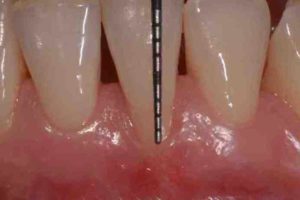

Questa procedura consente, dopo aver inciso la gengiva intorno al dente e scollato i tessuti molli, di accedere direttamente alla superficie radicolare eliminando i batteri presenti nelle zone più profonde e nascoste.

Verranno poi definite le eventuali terapie chirurgiche: